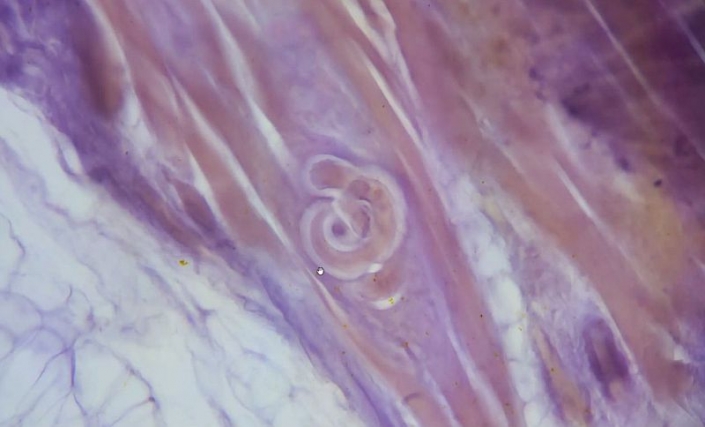

- Hauptthema heute: Trichinen. Bilder und Infos von Hans-Joachim Hoehland und Alfons Renz.

Trichinen sind trotz relativ geringer Artenzahl als Parasiten im Tierreich weit verbreitet. Verkapselt im Muskel der Wirte und durch deren Blutgefäße versorgt nisten sie sich dauerhaft ein und sind kaum angreifbar. Dabei gelingt es ihnen zu veranlassen, dass die Kapselwände vom Wirt (Muskel) selbst gebildet werden (und das bei unterschiedlichen Wirtsarten!).

Das Größenverhältnis zwischen der Kapsel und den Darmzotten wird in der Literatur meist nicht oder sogar falsch dargestellt. Alfons zeigts mit zwei Präparaten bei gleicher Vergrößerung.